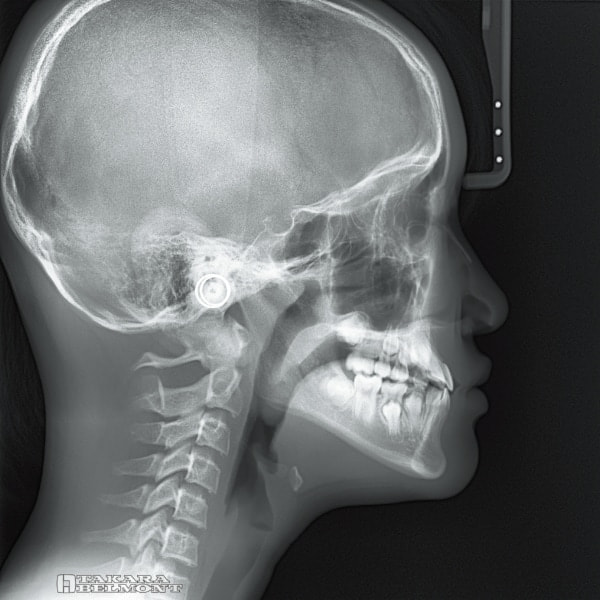

鮮明なセファロ画像を ワンショット撮影で

位置付け時のカメラスカウト機能で、撮影範囲を事前に確認。

0.5秒のワンショット撮影で、ブレの少ない鮮明なセファロ画像が取得できます。

セファロ撮影エリアを事前に確認できるカメラスカウト

位置付け時、X線管部に取り付けられたカメラ画像から、撮影範囲をタッチパネルで確認できます。

鮮明なセファロ画像を

0.5秒のワンショット撮影

最大管電圧100kV(最大管電流9mA)、0.5秒のワンショット撮影で、ブレによる影響を抑えた鮮明な画像が取得できます。

セファロ再構成

撮影後必要な時に、軟組織を強調、硬組織を強調した画像への再構成が可能です。

撮影モード(LA・PA・手根骨)ごとに、デフォルト設定できます。

撮影モード

LA撮影モード

六切りサイズ(W254×H203mm)より一回り大きい、最大W300×H250mmを含む3つの撮影エリアから選択できます。